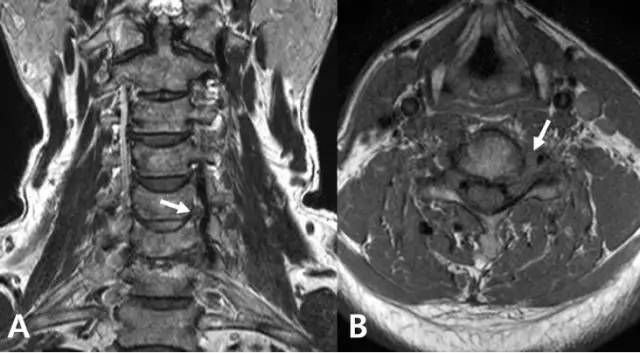

从影像学来看颈椎病为何会引起眩晕